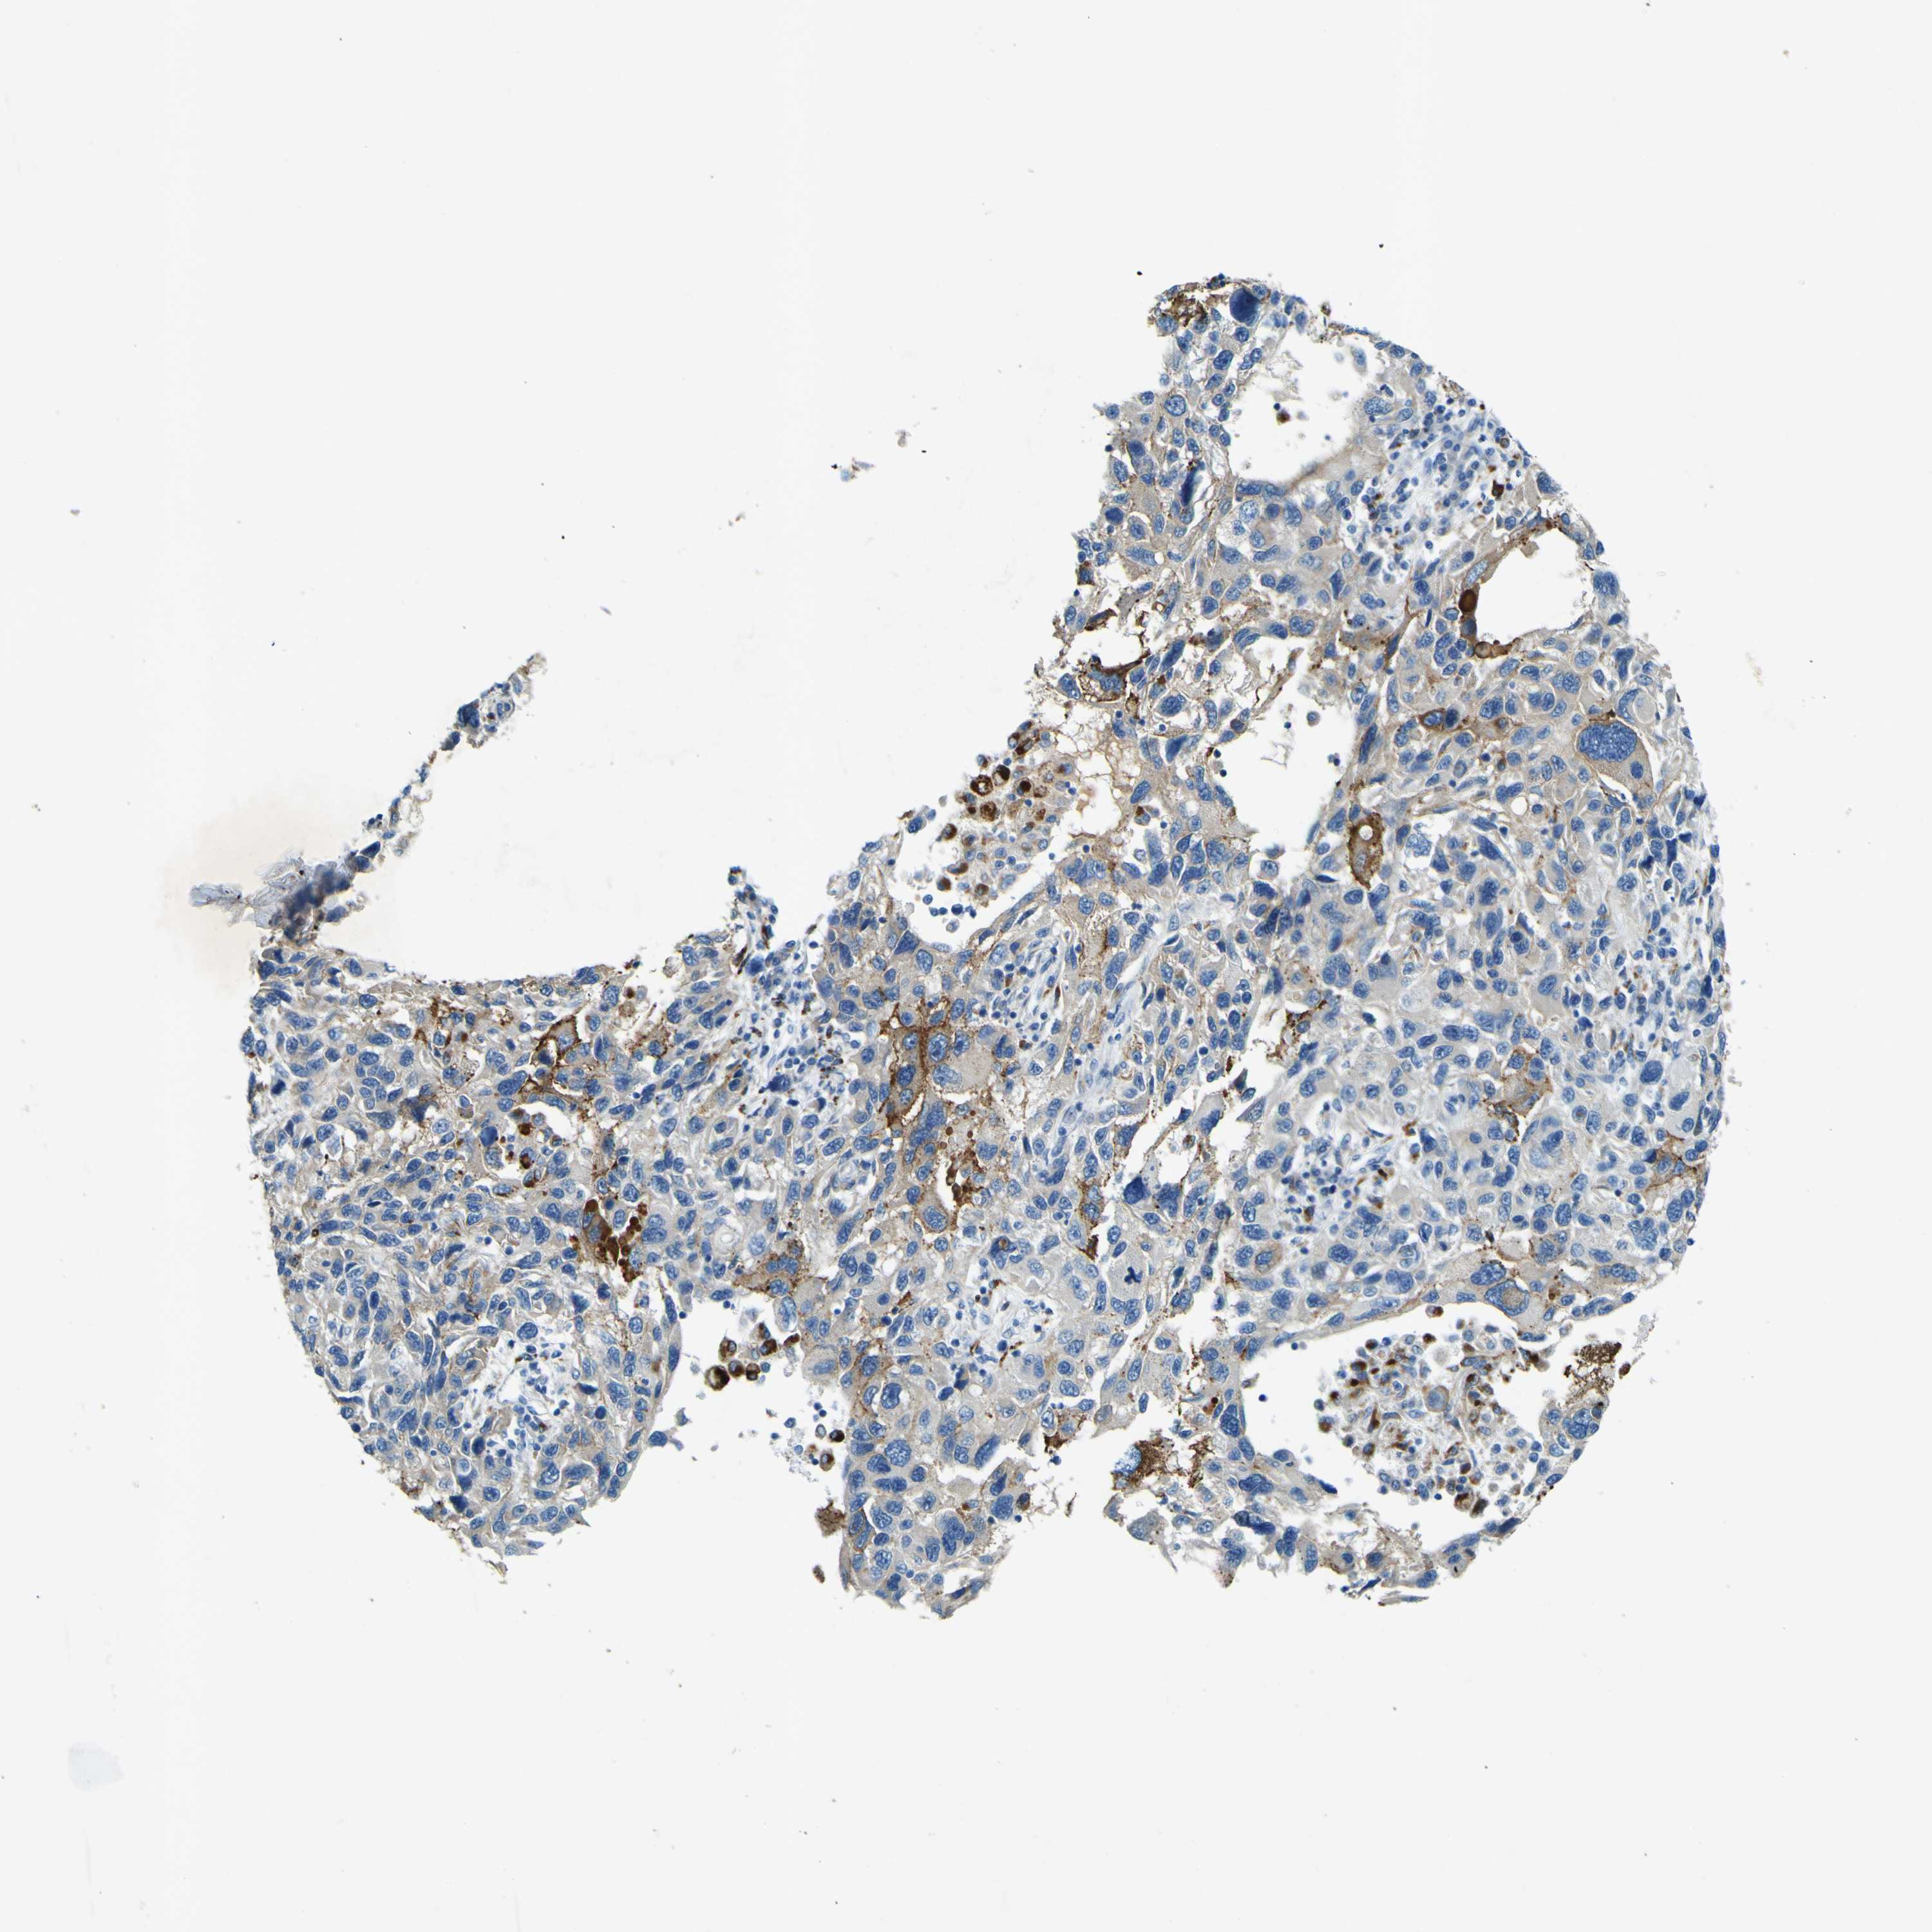

MELANOMA - Protein expressioni

A mouse-over function shows sample information and annotation data. Click on an image to view it in a full screen mode. Samples can be filtered based on level of antibody staining by selecting one or several of the following categories: high, medium, low and not detected. The assay and annotation is described here.

Note that samples used for immunohistochemistry by the Human Protein Atlas do not correspond to samples in the TCGA dataset.

Antibody stainingi

Antibody staining in the annotated cell types in the current human tissue is reported as not detected, low, medium, or high, based on conventional immunohistochemistry profiling in selected tissues. This score is based on the combination of the staining intensity and fraction of stained cells.

Each image is clickable and will lead to virtual microscopy that enables deeper exploration of all samples and also displays staining intensity scores, fraction scores and subcellular localization as well as patient and tissue information for each sample.

Antibody HPA011380

Staining

High

Medium

Low

Not detected

Intensity

Strong

Moderate

Weak

Negative

Quantity

>75%

75%-25%

<25%

None

Location

Nuclear

Cytoplasmic/membranous

Cytoplasmic/membranous,nuclear

Malignant melanoma, NOS

Malignant melanoma, Metastatic site